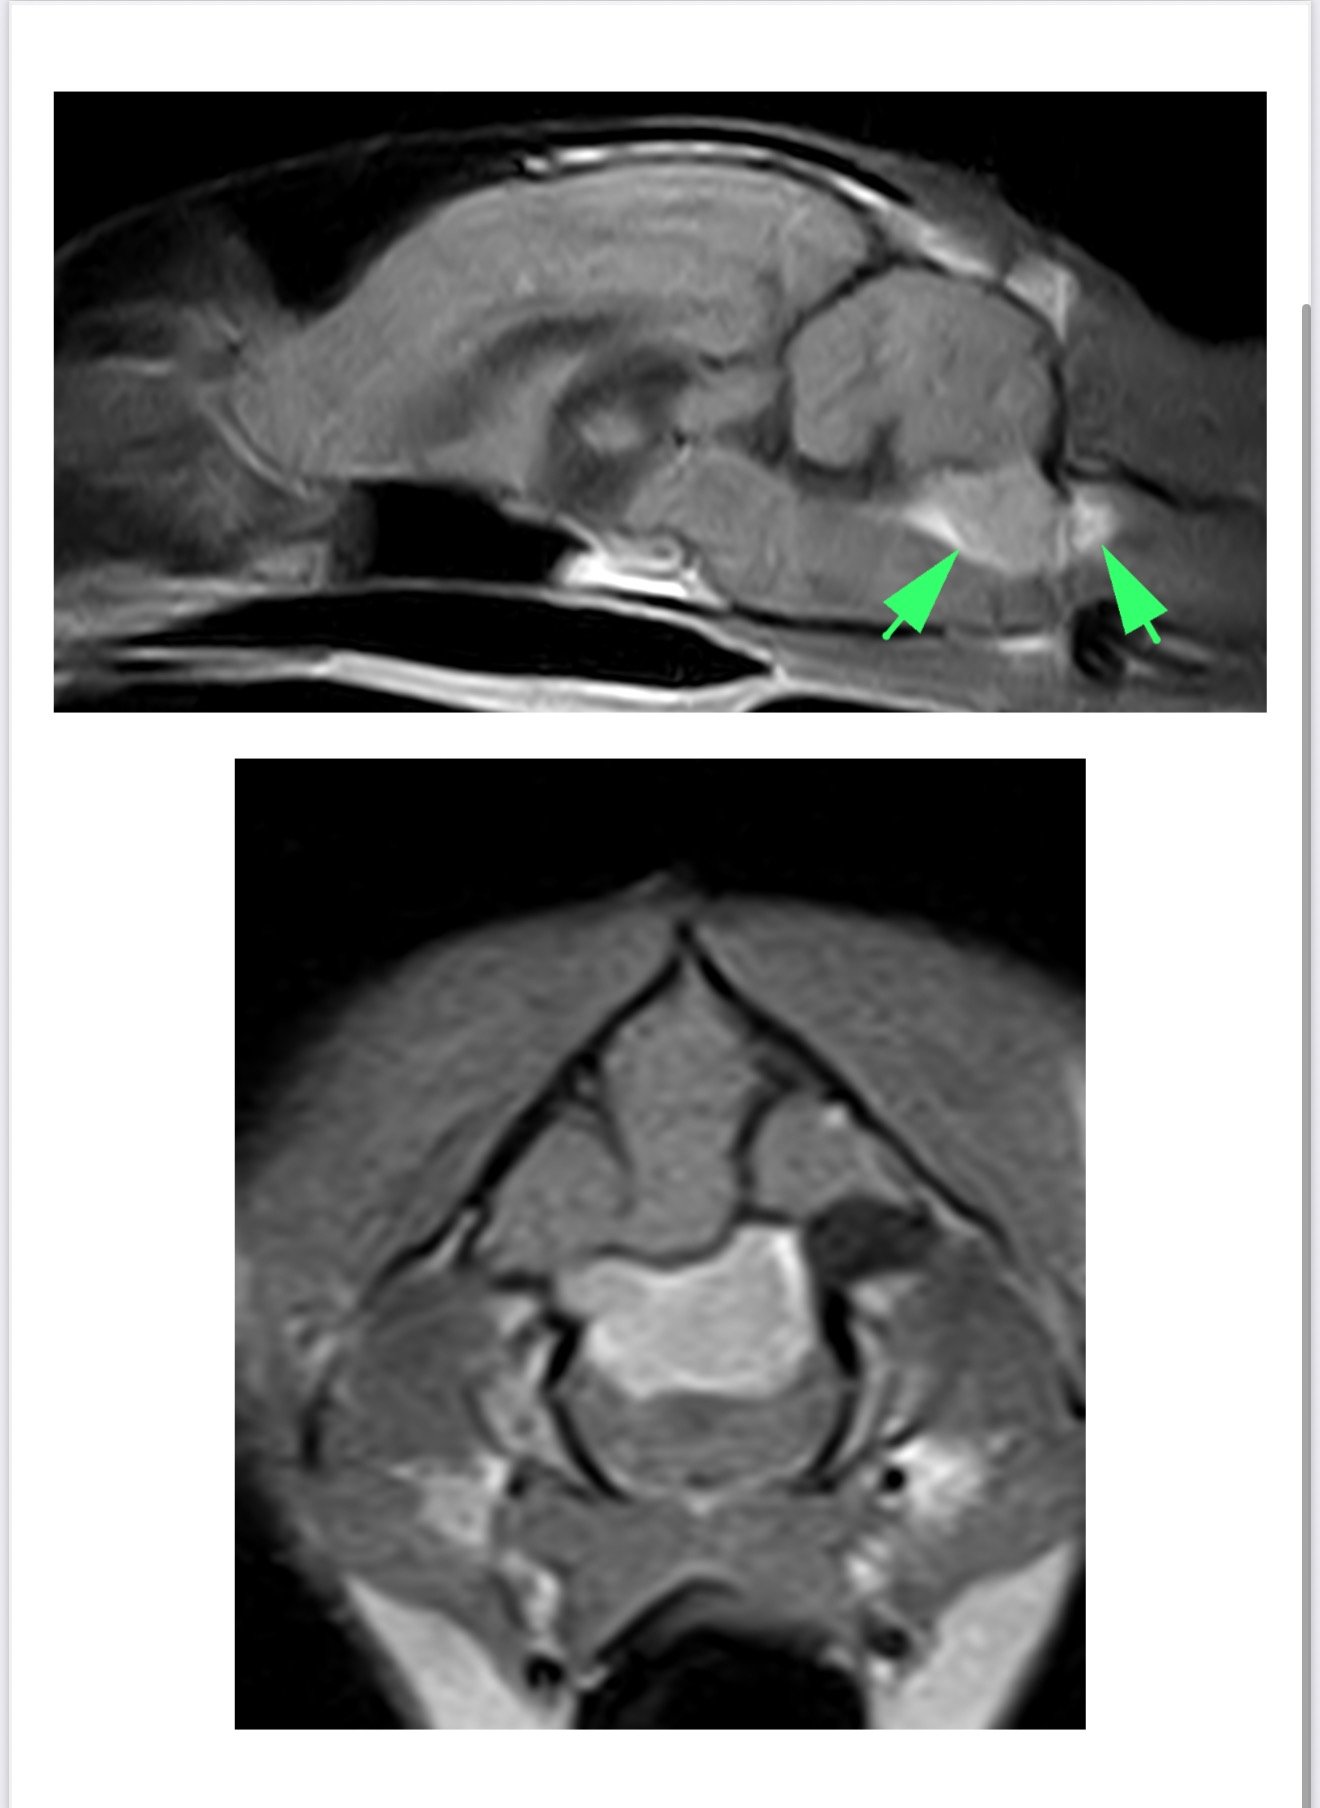

16.06.25 wykonaliśmy rezonans w Poznaniu w klinice Wąsiatycz, który wykazał nam zmianę w postaci oponiaka, niestety bez pobrania płynu ze względu na jego duży nadmiar, a doktor wskazał to jako przeciwwskazanie do wykonania tego zabiegu.